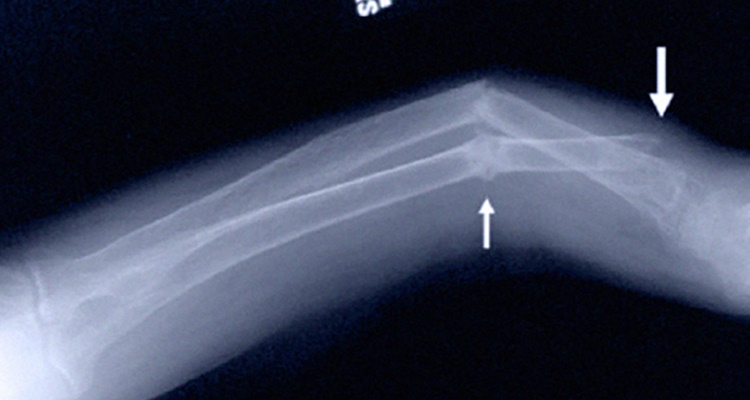

Con ella, y en conjunto con la osteoporosis o el mencionado ratiquismo que hemos visto, su carencia de puede aparecer también en enfermedades como la osteomalacia, el cual un trastorno en el que los huesos se vuelven más delgados y se presenta en adultos (rara vez en niños).

Es una enfermedad donde el músculo se debilita y los huesos se vuelven frágiles. Estos huesos, en parte sin vitaminas, pueden provocar una inclinación durante el crecimiento, especialmente en los huesos de las piernas que soportan el peso. Al mismo tiempo, esa osteomalacia en los adultos mayores puede provocar fracturas.